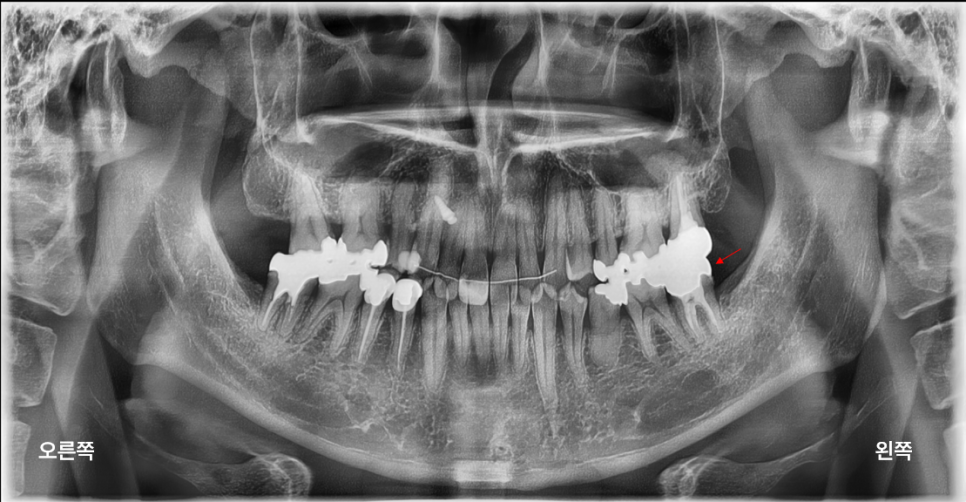

<치료를 많이 받은 여상호 원장…고등학교때 나를 괴롭혔던 치아는 왼쪽 아래 어금니>